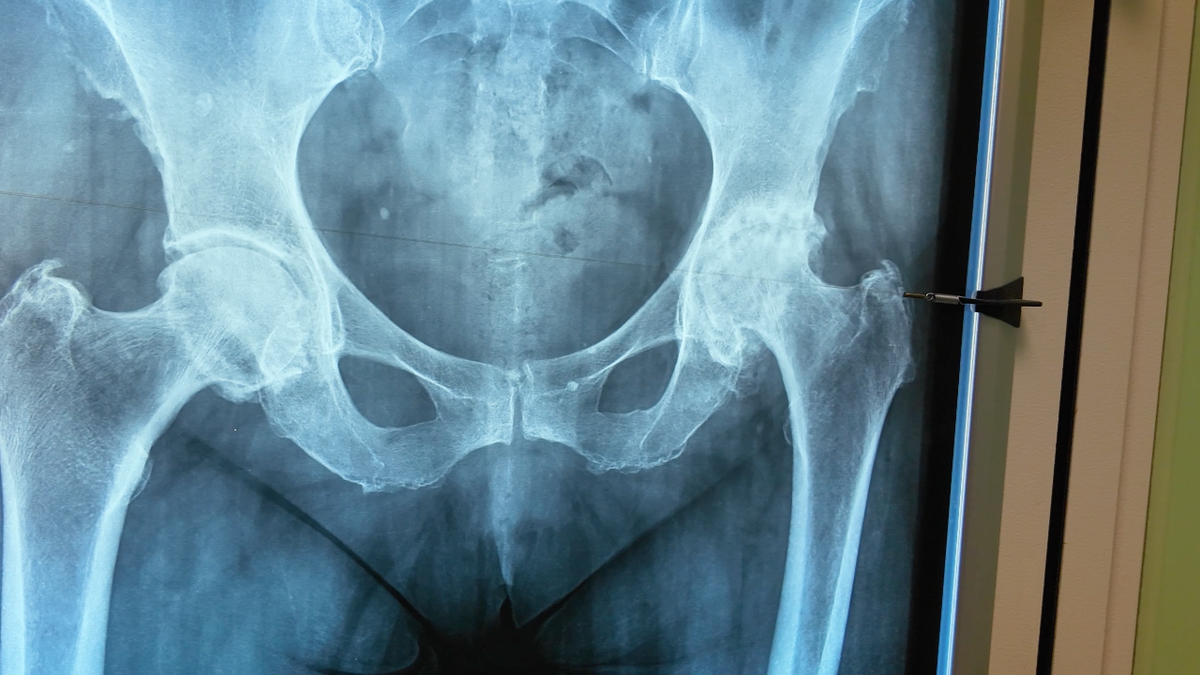

До операции. Разрушение тазобедренного сустава на снимке справа.

4 стадия по Келлгрену — это тяжёлое поражение:

• суставной хрящ разрушен почти полностью,

• кость трётся о кость,

• движения резко ограничены,

• боль появляется даже в покое.

На таком этапе сустав уже «не починить» таблетками или физиотерапией, ведь ткань, которой нет, вырастить невозможно.